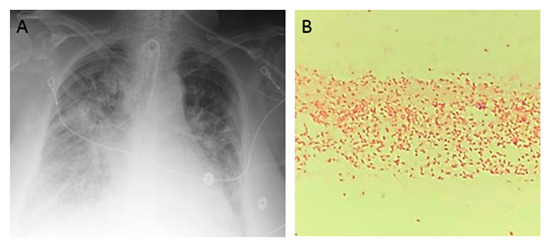

Figure 1.

An 85-year-old woman presented to the hospital after sustaining burn injuries and smoke exposure from a house fire. On admission, she was tachypneic, with a respiratory rate of 20 breaths per minute. Her physical exam was significant for 2nd degree burns along the dorsal and palmar aspects of her first three fingers on the right hand and partially on the index finger and thumb of her left hand. She had 1st degree burns on the rest of her hands and both forearms, as well as on the entire face and neck. Her wounds were debrided and silvedene was applied on her hands and forearms, while bacitracin was used for her face. Shortly after admission, the patient experienced difficulty breathing, trouble swallowing, voice changes and swelling around her mouth and tongue. She was intubated for airway protection and was transferred to the intensive care unit (ICU). She was extubated 2 days later, but re-intubated after an episode of projectile vomiting and aspiration. Due to the development of fevers, blood and urine cultures were taken. She was started on cefepime 2 g every 12 h and vancomycin 15 mg/kg every 12 h for aspiration pneumonia. Blood culture grew methicillin-sensitive Staphylococcus aureus and urine culture was positive for Morganella morganii. Four days later, she developed spontaneous pneumothorax that required chest tube placement. Persistence of fever and worsening leukocytosis prompted antibiotic escalation to meropenem with continuation of vancomycin. Over the next 2 days, the patient developed acute renal failure and was started on continuous veno-venous hemodialysis. She completed 12 days of antibiotics. Over the next week, she developed a central line bloodstream infection caused by Enterococcus faecalis and ventilator associated pneumonia caused by methicillin-sensitive Staphylococcus aureus, for which she was treated with ampicillin/sulbactam for 7 days. Three days later, the patient developed a new episode of fever and worsening bilateral infiltrates in chest X-ray (A). Cultures were obtained, and gram stain from blood culture and endotracheal aspirate revealed gram-negative bacilli (B). The Mac Conckey agar demonstrated a pink color, which is characteristic of lactose-fermenting organisms (C). The patient was started empirically on cefepime 2 g every 12 h, and the central lines were removed (one of the potential sources of infection). The gram-negative rod was identified as Raoultella planticola by MALDI-TOF (matrix-assisted laser desorption ionization time of flight), and further in-vitro susceptibility testing by the Vitek® 2 system (BioMérieux, Inc., Hazelwood, MO, USA) revealed resistance to most antibiotics, except for colistin, polymyxin B, aminoglycosides, tetracycline, and tigecycline (D). We performed additional phenotypic tests and detected carbapenemase production by the Carbapenem Inactivation Method (E). Supplementary antibiotic susceptibility studies by E-test showed susceptibility to ceftazidime/avibactam (F, left side) and meropenem/vaborbactam (F, right side). Confirmation of carbapenemase production was carried out by genotypic analysis using Verigene system (Luminex Corp, Austin, TX, USA), which identified blaKPC and blaCTX-M genes. Treatment with cefepime was discontinued and the patient was started on combination therapy with ceftazidime/avibactam and polymyxin B. Follow-up blood cultures were negative and her respiratory status improved over the following days. Finally, she was transferred to a LTAC (long-term acute care) facility to complete 2 weeks of antibiotic therapy.